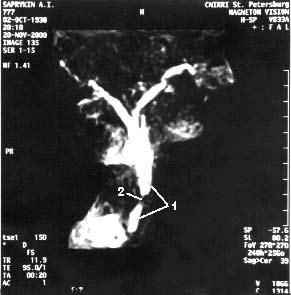

В последние годы появился новый неинвазивный метод – магнитно-резонансная холангиопанкреатография который позволяет визуализировать желчные и панкреатические протоки без инвазивных вмешательств и введения контрастных веществ. Это исследование осуществимо у всех больных, не дает осложнений и позволяет получить такую же информацию, как и при одновременном применении КТ, ангиографии (АГ) и эндоскопическая ретроградная холангиопанкеатография (ЭРХПГ) (рис. 101. а, б).

Рис. 101. Магнитнорезонансная холангиопанкреатикография. Рак головки ПЖ. А – отмечается дефект наполнения (2) в панкреатической части холедоха (1) на протяжении 1 см. Опухоль диаметром 1,5 см была выявлена только интраоперационно. Б – отмечается дефект (3) в месте слияния общего желчного (1) и панкреатического (2) протоков. Имеется супрастенотическое расширение протоков. Опухоль диаметром 3 см была выявлена при УЗИ, КТ и интраоперационно